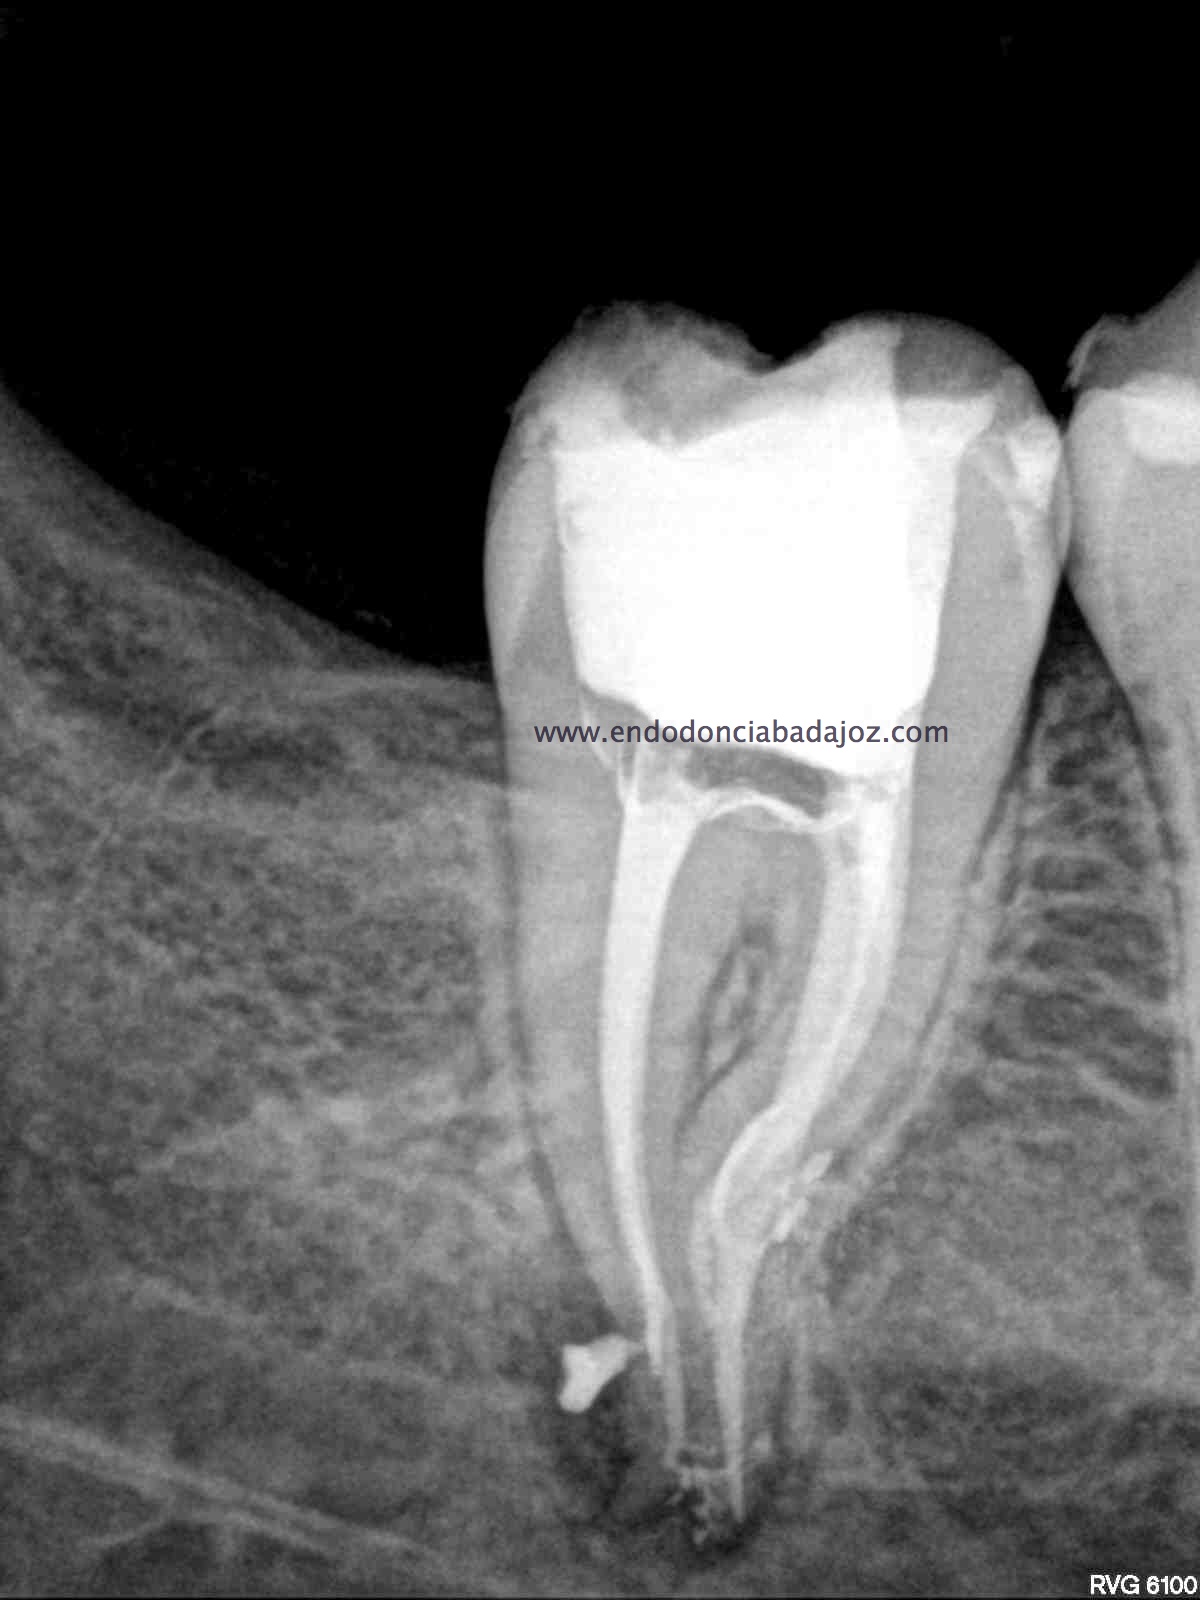

Sistemas de Conductos de un 4.7

Nos remiten a  la clínica una pieza 4.7, con necrosis pulpar y afectación periodontal, periodontitis apical:

La anatomía de los conductos nos hacia sospechar de un caso algo más complicado. Lo más complicado fue mantener la permeabilidad de los conductos. Instrumentamos con sistema rotatorio de Mtwo, mucha irrigación, se usó Irrisafe en los últimos lavajes, y como sistema de obturación usamos Condensación vertical con ola contínua, haciendo un backfilling con la Pistola Obtura II.